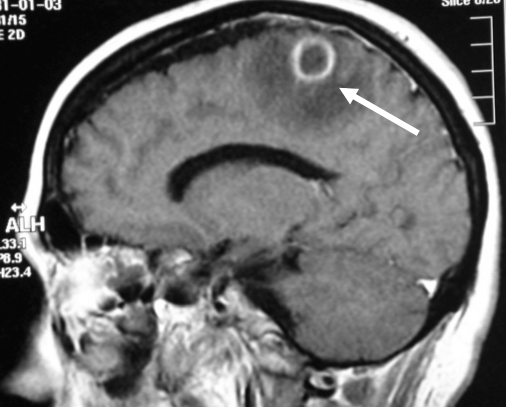

Absceso cerebral

Es una acumulación de células inmunitarias, pus y otros materiales en el cerebro, generalmente a raíz de una infección bacteriana o micótica.

Los abscesos cerebrales comúnmente ocurren cuando las bacterias u hongos infectan parte del cerebro. Como resultado, se presenta hinchazón e irritación (inflamación). Las células cerebrales infectadas, los glóbulos blancos, al igual que las bacterias u hongos vivos y muertos se acumulan en una zona del cerebro. Se forma tejido alrededor de esta zona y crea una masa o un absceso.